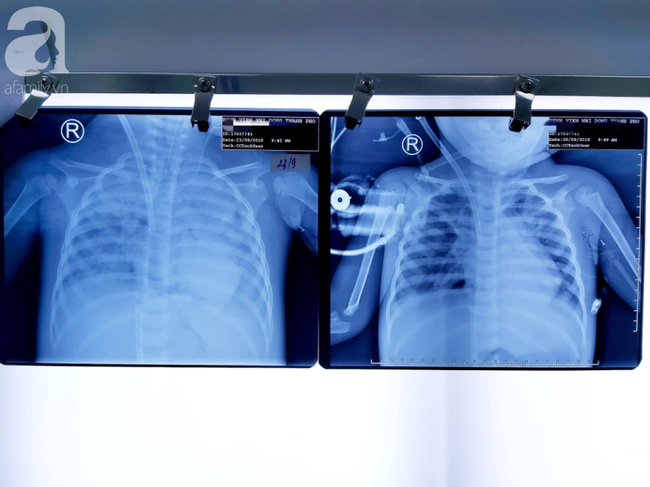

06/10/2019 16:11Bác sĩ dùng phương pháp 'hồi sinh tim phổi' cứu bé gái 30 tháng tuổi nguy kịch vì viêm phổi cực nặng

Đó là trường hợp của bé T.N.P.L. (30 tháng tuổi, ngụ quận 4, TP.HCM).

Theo bệnh sử, bé bị viêm phổi nặng, phải nhập 2 bệnh viện (BV) lớn tại TP.HCM nhưng tình trạng không cải thiện mà sốt cao liên tục, viêm phổi nặng dần, sốt co giật, suy hô hấp tiến triển.

Bệnh nhi khởi phát thêm cơn suyễn nặng, sức thở của em đuối dần, tổn thương phổi trắng xóa và phổi không thể trao đổi khí thêm được nữa.

Trước tình trạng nguy hiểm, bé được đặt nội khí quản rồi chuyển đến BV Nhi đồng Thành phố.

Lúc này, bệnh nhi đã đi vào trạng thái sốc, tụt huyết áp, tiên lượng rất xấu, độ bão hòa oxy trong máu chỉ còn 60%.

Tại khoa Hồi sức tích cực - Chống độc (ICU), các bác sĩ tiến hành hội chẩn khẩn, đồng thời xin ý kiến Ban Giám đốc và thống nhất chỉ định triển khai áp dụng kỹ thuật trao đổi oxy màng ngoài cơ thể (ECMO) cho bệnh nhân.

Ekip mạch máu phối hợp nhịp nhàng cùng ekip ICU xẻ mạch máu, luồn canula và kết nối hoàn chỉnh vào cơ thể bệnh nhi.

Sau 8 ngày điều trị tình trạng bá tiến triển tốt dần. Em được ngưng hết thuốc vận mạch hỗ trợ tuần hoàn, giảm đáng kể thông số thở máy và rút ống nội khí quản ngay sau khi vừa cai ECMO.

Hiên bệnh nhi đã gần như bình phục hoàn toàn và trở lại cuộc sống bình thường.

BS Lê Vũ Phượng Thy, trưởng khoa ICU cho biết đây là một trong những trường hợp hiếm hoi được bỏ thở máy ngay sau khi chạy ECMO.

Kỹ thuật này được áp dụng cho những trường hợp bệnh nhân bị suy hô hấp nặng do tổn thương phổi hoặc trụy tim, suy tuần hoàn nặng đáp ứng kém hoặc không còn đáp ứng với các biện pháp hồi sức thông thường.

Đây chính là biện pháp cuối cùng, là tia hy vọng cho những bệnh nhân đang cận kề cái chết.

Được biết, bé L. là trẻ viêm phổi nặng kèm suyễn, nguy kịch, suy hô hấp cấp tiến triển đầu tiên được thực hiện ECMO tại một trung tâm nhi khoa tại miền Nam Việt Nam.